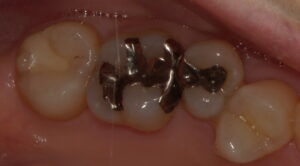

おそらく術前の保険診療では2,3分で詰めたと思いますが、今回この歯は防湿から精密充填まで20分ほどかかっております。